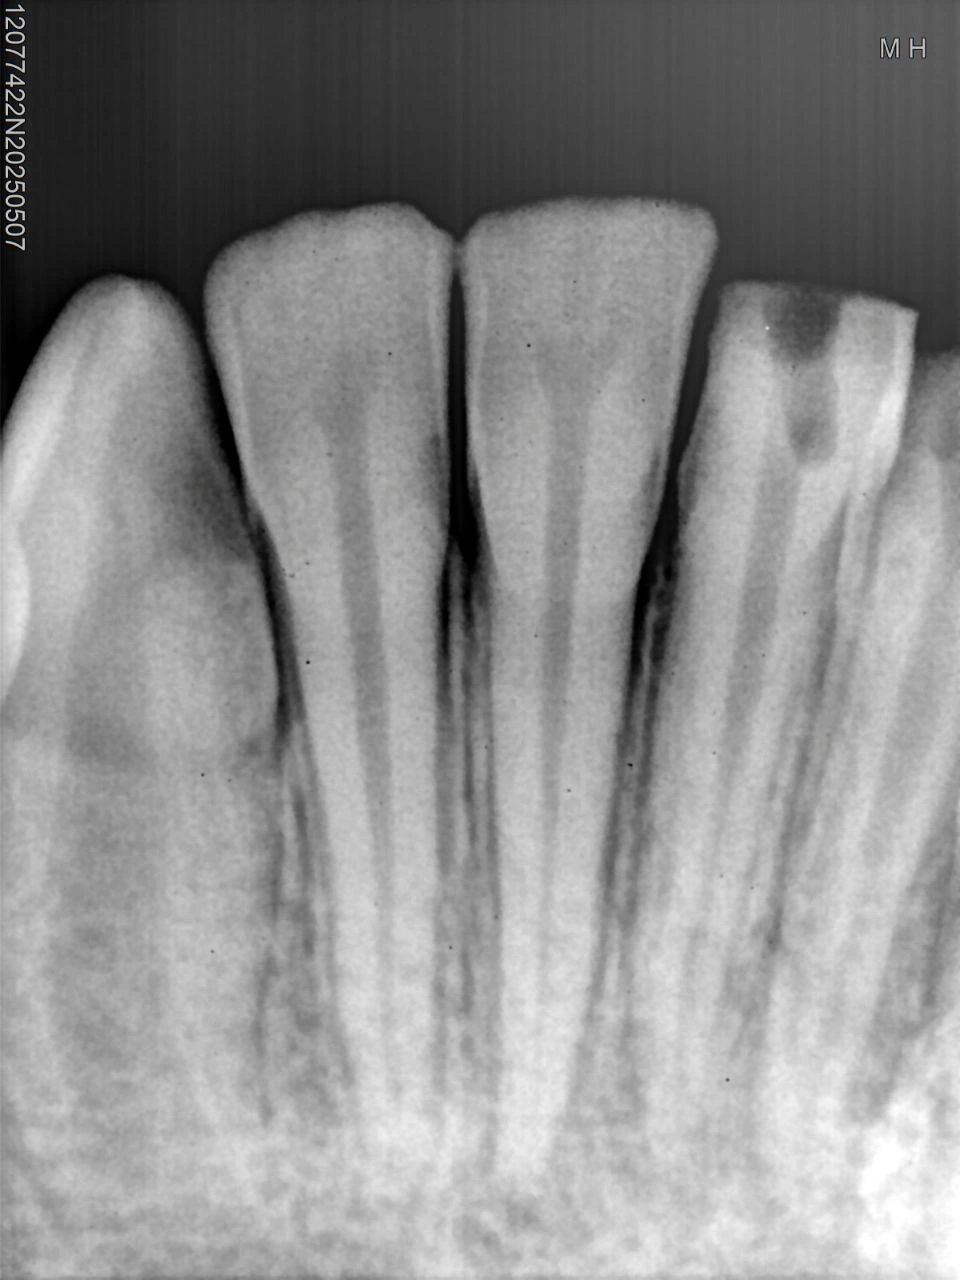

Clinical Cases